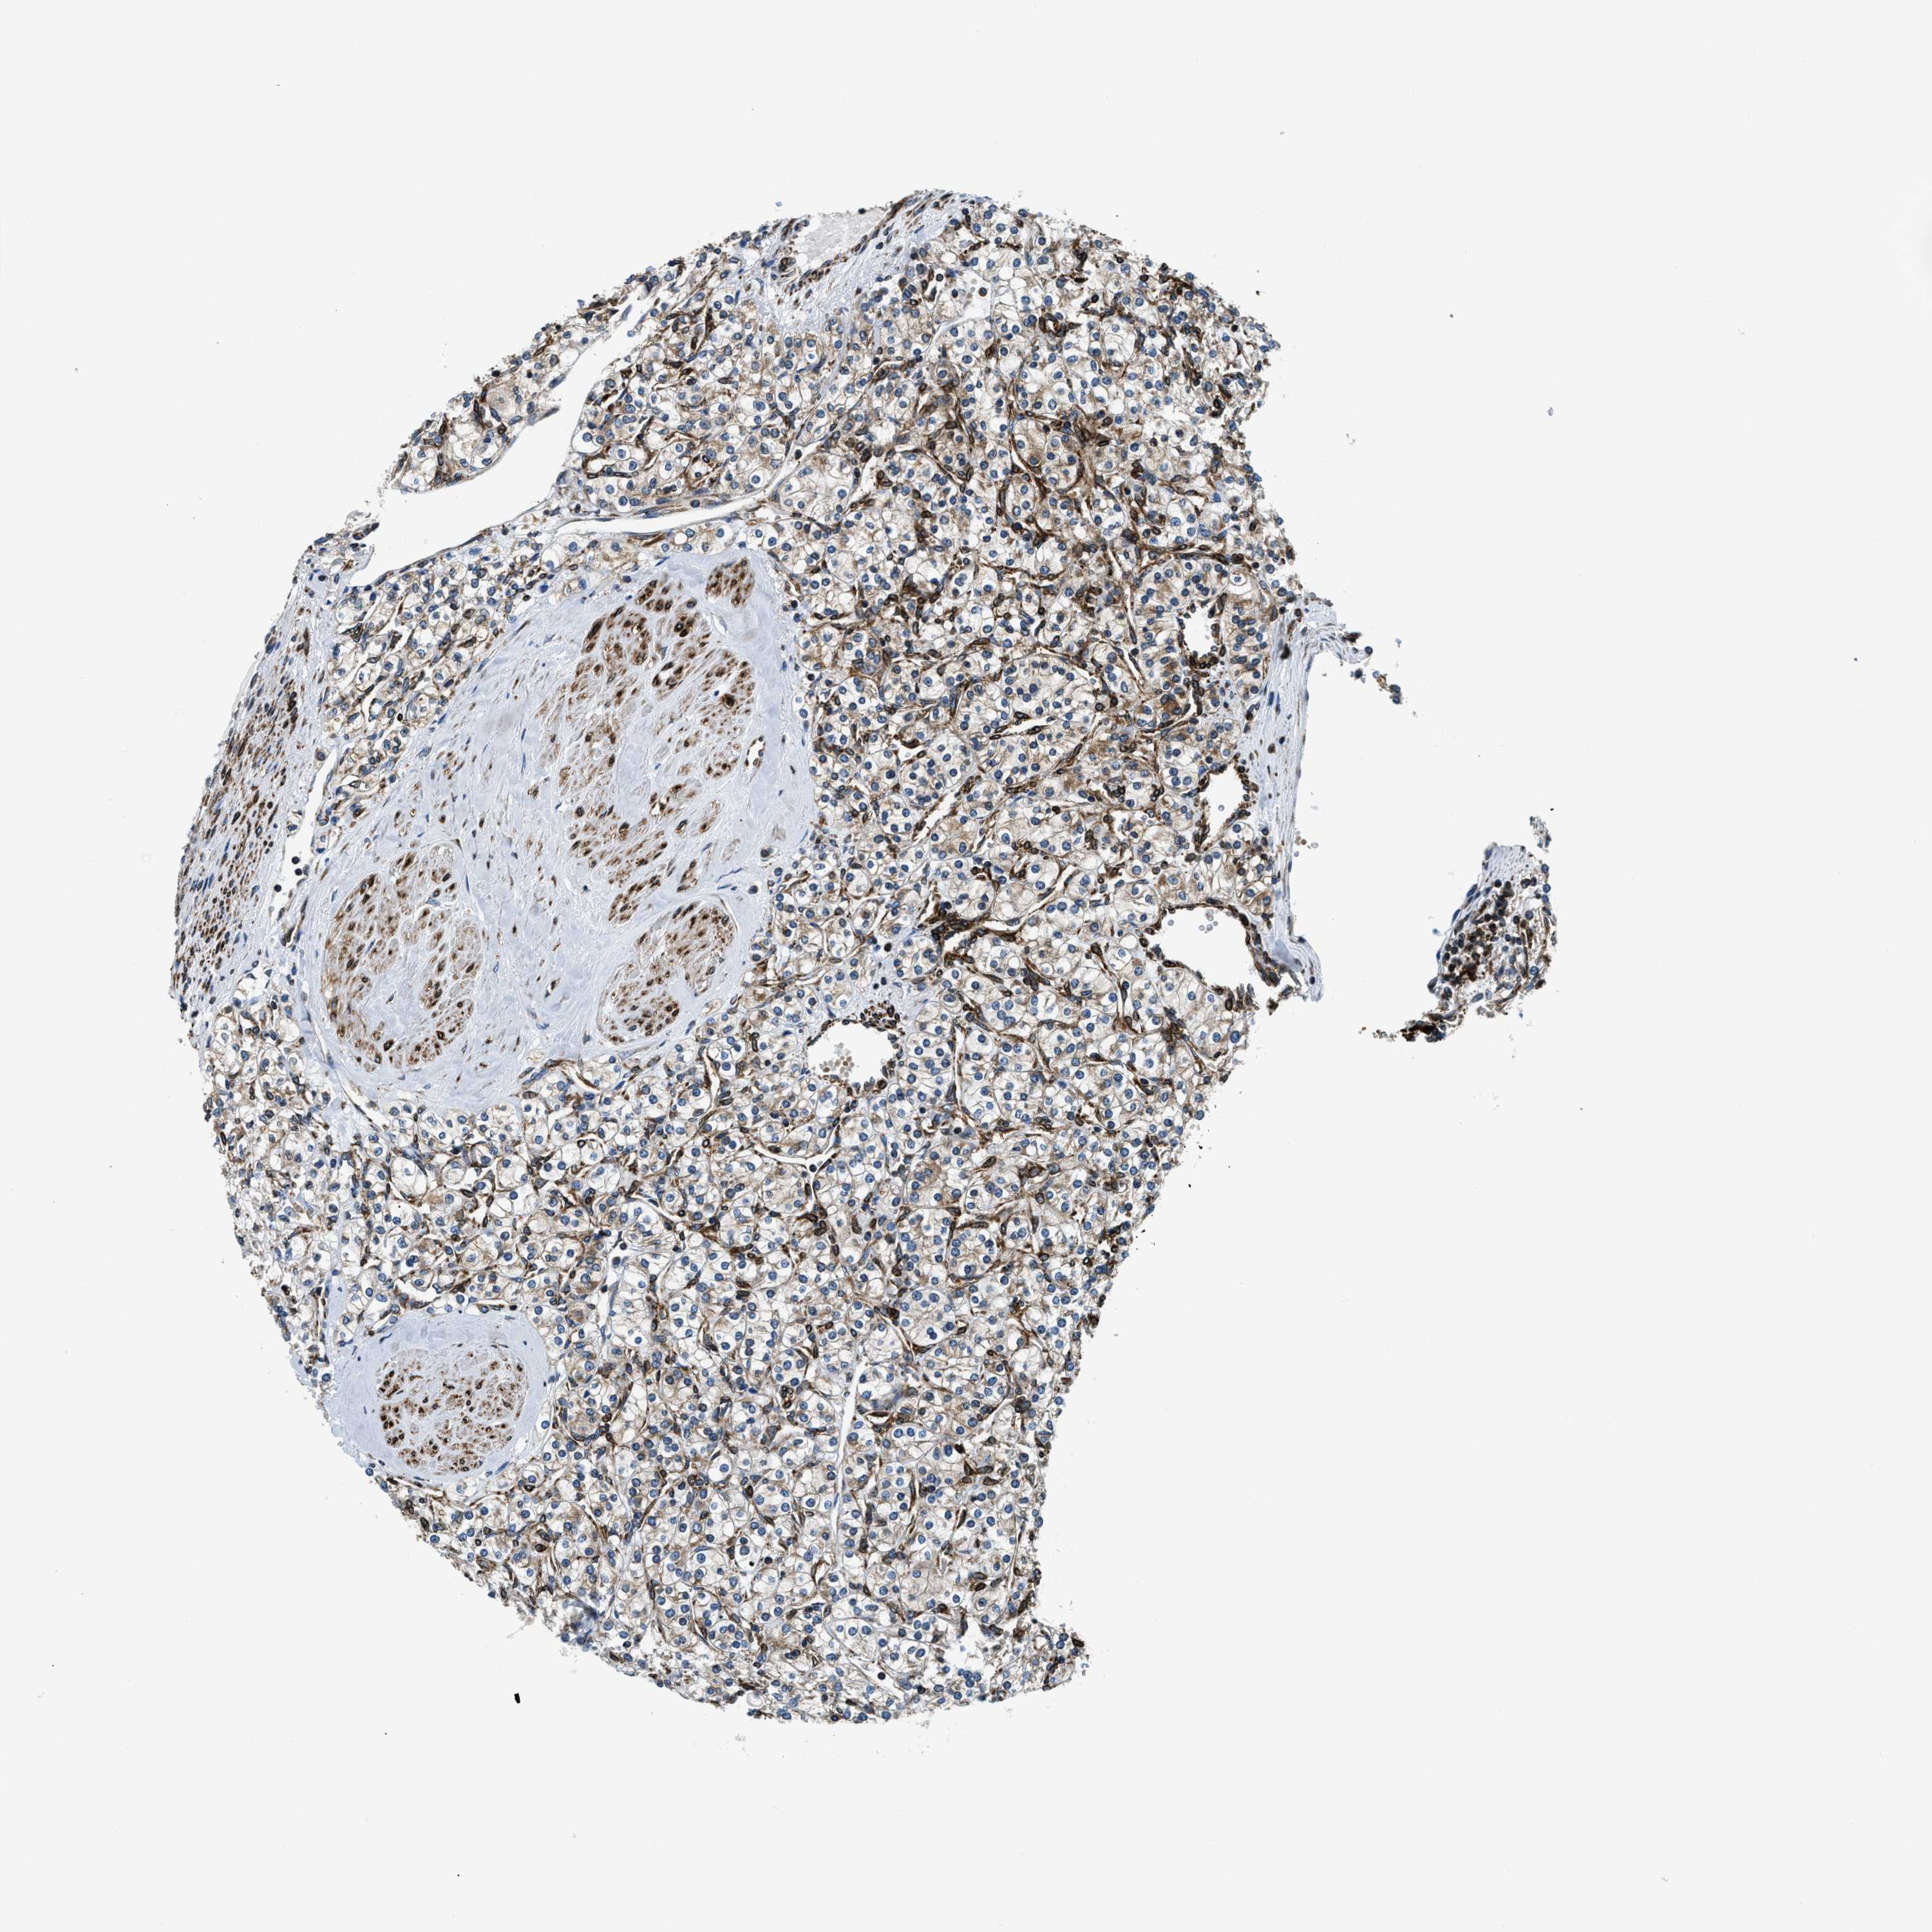

KIDNEY RENAL CLEAR CELL CARCINOMA (TCGA) - Interactive survival scatter ploti

The Survival Scatter plot shows the clinical status (i.e. dead or alive) for all individuals in the patient cohort, based on the same data that underlies the corresponding Kaplan-Meier plots. Patients that are alive at last time for follow-up are shown in blue and patients who have died during the study are shown in red.

The x-axis shows the expression levels (FPKM) of the investigated gene in the tumor tissue at the time of diagnosis. The y-axis shows the follow-up time after diagnosis (years). Both axes are complimented with kernel density curves demonstrating the data density over the axes. The top density plot shows the expression levels (FPKM) distribution among dead (red) and alive patients (blue). The right density plot shows the data density of the survived years of dead patients with high and low expression levels respectively, stratified using the cutoff indicated by the vertical dashed line through the Survival Scatter plot. This cutoff is automatically defined based on the FPKM cutoff that minimizes the p-score. The cutoff can be changed by dragging the vertical line or by entering a cutoff value in the square labeled "Current cut-off".

Under the Survival Scatter plot the p-score landscape (black curve; left axis) is shown together with dead median separation (red curve; right axis). Dead median separation is the difference in median mRNA expression between patients who have died with high and low expression, respectively. It is calculated as follows: median FPKM expression of dead patients with high expression - median FPKM expression of dead patients with low expression. This is intended to aid the user in visually exploring custom cutoffs and the associated p-scores and dead median separation.

Individual patient data is displayed and can be filtered by clicking on one or more of the category buttons on the top of the page. Categories describing expression level and patient information include: high, low, alive, dead, female, male and tumor stages. The scale of the x-axis can be toggled between linear and log-scale by clicking on the "x log" button. Mouse-over function shows TCGA ID, patient information and mRNA expression (FPKM) for each patient.

& Survival analysisi

Kaplan-Meier plots summarize results from analysis of correlation between mRNA expression level and patient survival. Patients were divided based on level of expression into one of the two groups "low" (under cut off) or "high" (over cut off). X-axis shows time for survival (years) and y-axis shows the probability of survival, where 1.0 corresponds to 100 percent.

CDS2 is validated prognostic, high expression is favorable in Kidney Renal Clear Cell Carcinoma (TCGA)

Best expression cut offi

Based on the FPKM value of each gene, patients were classified into two groups and association between prognosis (survival) and gene expression (FPKM) was examined. The best expression cut-off refers the FPKM value that yields maximal difference with regard to survival between the two groups at the lowest log-rank P-value. Best expression cut-off was selected based on survival analysis .

When clicking on this number, the vertical dashed line indicating cut-off, the interactive survival plot, and the Kaplan-Meier curve will be adjusted to show results based on the best expression cut-off.

: 19.31

TCGA RNA samplesi

RNA-seq data is reported as average FPKM (number Fragments Per Kilobase of exon per Million reads), generated by the The Cancer Genome Atlas (TCGA) .

Normal distribution across the dataset is visualized with box plots, shown as median and 25th and 75th percentiles. Points are displayed as outliers if they are above or below 1.5 times the interquartile range. FPKM values of the individual samples are presented next to the box plot.

Average pTPM 15.8

Number of samples 521